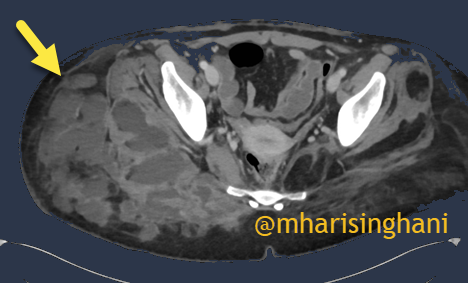

22 year old has liposuction at a "health spa"; comes with gluteal abscess

19 116